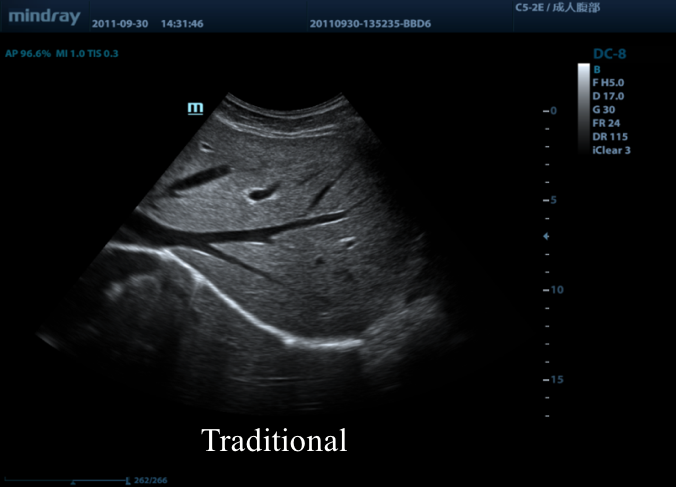

Предлагаем вам ознакомиться с примером применения данной технологии. Изображения выполнены на приборе Mindray DC-8, на верхнем изображении режим iBeam (компаундинг) отключен, а на нижнем включен на первую ступень регулировки (3 луча).